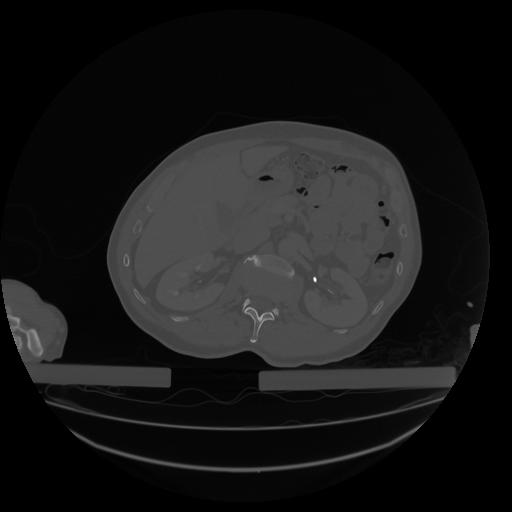

34 CUERPO,CE,Vol,1.0,CUERPO,,